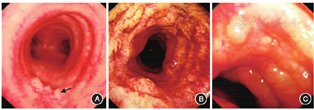

所收集11例患者中,1例患者支气管镜检查未见明显异常表现,10例累及气管和(或)支气管,2例伴肺部病变,8例不伴肺部病变。其中,2例(2/10)支气管镜下表现为气管支气管黏膜局部或散在病变(图2A),2例(2/10)支气管镜下可见气管弥漫性充血肿胀,多发结节样隆起,管腔无狭窄(图2B)。6例(6/10)支气管镜下可见不同程度的黏膜隆起、肥厚、结节以及管腔狭窄(图2C)。早、中、晚期各为2、2、6例。

注:A.气管散在结节样隆起(箭头所示);B.气管弥漫性充血肿胀,多发结节样隆起,管腔无狭窄;C.气管黏膜显著肿胀肥厚,结节样隆起致管腔显著狭窄